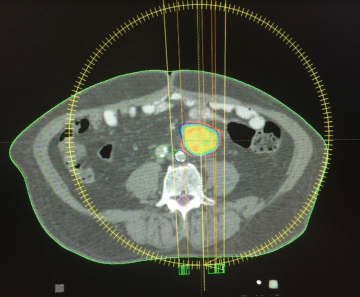

En 2015, especialistas del HOMS practicaron de manera exitosa la primera técnica de radiocirugía extracraneal, con avanzada tecnología en su Centro del Cáncer. La práctica se realizó en un paciente con metástasis ganglionar de primario colorrectal, utilizando PET-CT y tomografía de abdomen y pelvis con doble contraste, fusión de ambas imágenes y posterior verificación antes del tratamiento, mediante imágenes tomográficas del blanco a tratar.